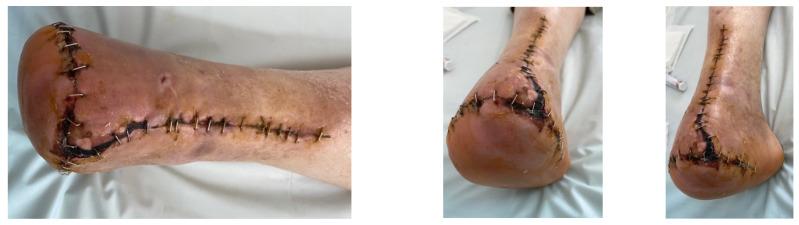

: Revascularization based on the angiosome concept (AC) is a controversial subject because there is currently no clear evidence of its efficacy, due to the heterogeneity of patients (multiple and diverse risk factors and comorbidities, multiple variations in the affected angiosomes). Choke vessels change the paradigm of the AC, and the presence or absence of the plantar arch directly affects the course of targeted revascularization. The aim of this study was to evaluate the effect of revascularization based on the AC in diabetic patients with chronic limb-threatening ischemia (CLTI). This retrospective analysis included 51 patients (40 men, 11 women), with a mean age of 69 years (66-72) and a total of 51 limbs, who presented with Rutherford 5-6 CLTI, before and after having undergone a drug-coated balloon angioplasty (8 patients) or plain balloon angioplasty (43). Between November 2018 and November 2019, all patients underwent below-the-knee balloon angioplasties and were followed up for an average of 12 months. The alteration of microcirculation was compared between directly and indirectly revascularized angiosomes. The study assessed clinical findings and patient outcomes, with follow-up investigations, comparing wound healing rates between the different revascularization methods. Patient records and periprocedural leg digital subtraction angiographies (DSA) were analyzed. Differences in outcomes after direct revascularization and indirect percutaneous transluminal angioplasty (PTa) were examined using Cox proportional hazards analysis, with the following endpoints: ulcer healing, limb salvage, and also amputation-free survival. Direct blood flow to the angiosome supplying the ulcer area was achieved in 38 legs, in contrast to 13 legs with indirect revascularization. Among the cases, there were 39 lesions in the anterior tibial artery (ATA), 42 lesions in the posterior tibial artery (PTA), and 8 lesions in the peroneal artery (PA). According to a Cox proportional hazards analysis, having fewer than three (<3) affected angiosomes (HR 0.49, 95% CI 0.19-1.25, = 0.136) was associated with improved wound healing. Conversely, wound healing outcomes were least favorable after indirect angioplasty ( = 0.206). When adjusting the Cox proportional hazard analysis for the number of affected angiosomes, it was found that direct drug-coated angioplasty resulted in the most favorable wound healing ( = 0.091). At the 1-year follow-up, the major amputation rate was 17.7%, and, according to a Cox proportional hazards analysis, atrial fibrillation (HR 0.85, 95% CI 0.42-1.69, = 0.637), hemodialysis (HR 1.26, 95% CI 0.39-4.04, = 0.699), and number of affected angiosomes > 3 (HR 0.94, 95% CI 0.63-1.39, = 0.748) were significantly associated with poor leg salvage. Additionally, direct endovascular revascularization was associated with a lower rate of major amputation compared to indirect angioplasty (HR 1.09, 95% CI 0.34-3.50, = 0.884). Observing the angiosomes concept in decision-making appears to result in improved rates of arterial ulcer healing and leg salvage, particularly in targeted drug-coated balloon angioplasty for diabetic critical limb ischemia, where multiple angiosomes are typically affected.

基于血管体概念(AC)的血运重建是一个有争议的话题,因为目前尚无明确证据证明其疗效,这是由于患者存在异质性(多种不同的风险因素和合并症,受累血管体存在多种变异)。窒息血管改变了AC的模式,足底弓的存在与否直接影响靶向血运重建的进程。本研究的目的是评估基于AC的血运重建对慢性肢体威胁性缺血(CLTI)糖尿病患者的影响。这项回顾性分析纳入了51例患者(40例男性,11例女性),平均年龄69岁(66 - 72岁),共51条肢体,这些患者在接受药物涂层球囊血管成形术(8例)或普通球囊血管成形术(43例)前后均表现为卢瑟福5 - 6级CLTI。在2018年11月至2019年11月期间,所有患者均接受了膝下球囊血管成形术,并平均随访12个月。比较了直接和间接血运重建血管体之间的微循环变化。该研究评估了临床发现和患者预后,并通过随访调查比较了不同血运重建方法之间的伤口愈合率。分析了患者记录和围手术期腿部数字减影血管造影(DSA)。使用Cox比例风险分析检查直接血运重建和间接经皮腔内血管成形术(PTa)后结局的差异,终点如下:溃疡愈合、肢体挽救以及无截肢生存率。38条腿实现了向供应溃疡区域的血管体的直接血流,相比之下,13条腿为间接血运重建。在这些病例中,胫前动脉(ATA)有39处病变,胫后动脉(PTA)有42处病变,腓动脉(PA)有8处病变。根据Cox比例风险分析,受累血管体少于三个(<3)(HR 0.49,95%CI 0.19 - 1.25,P = 0.136)与伤口愈合改善相关。相反,间接血管成形术后伤口愈合结局最不理想(P = 0.206)。在对受累血管体数量进行Cox比例风险分析调整后,发现直接药物涂层血管成形术导致最有利的伤口愈合(P = 0.091)。在1年随访时,大截肢率为17.7%,根据Cox比例风险分析,心房颤动(HR 0.85,95%CI 0.42 - 1.69,P = 0.637)、血液透析(HR 1.26,95%CI 0.39 - 4.04,P = 0.699)以及受累血管体数量>3(HR 0.94,95%CI 0.63 - 1.39,P = 0.748)与肢体挽救不佳显著相关。此外,与间接血管成形术相比,直接血管内血运重建与较低的大截肢率相关(HR 1.09, 95%CI 0.34 - 3.50, P = 0.884)。在决策过程中遵循血管体概念似乎能提高动脉溃疡愈合率和肢体挽救率,特别是在针对糖尿病严重肢体缺血的靶向药物涂层球囊血管成形术中,此时多个血管体通常会受累。